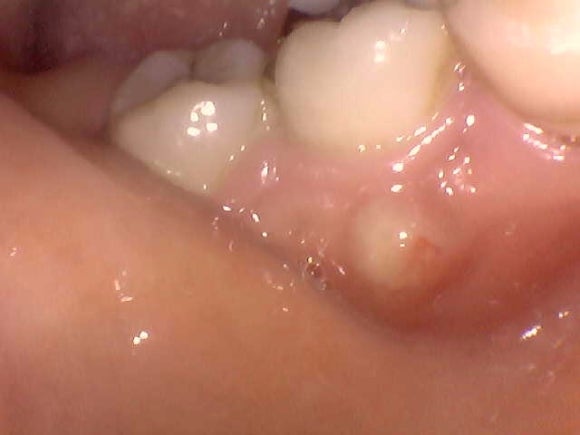

위 파노라마 사진의 실제 구강 내 사진

사진 상 왼쪽 맨 끝에서 두번 째 어금니 뿌리 주변으로

뼈가 녹아내리고 있는 것을 볼 수 있습니다.

실제 구강 내 사진에서는 붓기가 관찰 됩니다.

해당 케이스의 경우 치아의 모빌리티가 매우 심했으며,

누르는 순간 치아가 움푹 움푹 들어가고 노란 농 (PUS)의 배출도 관찰 되었습니다.

증상은 없어서 환자가 심각한 정도인지 인지를 하지 못했지만,

저를 신뢰하시는 분이었기 때문에

미리 발치를 하여 감염이 더 퍼지지 않도록 방지를 한 케이스 입니다.